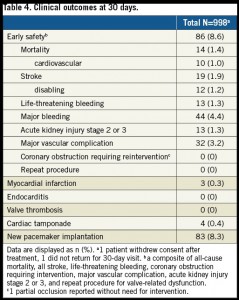

30日後の死亡率は1.4%,脳卒中は1.9%,新規ペースメーカーの留置は8.3%であった。

今回のレジストリーの結果では30日死亡率、後遺症の残る脳卒中の発生率は以前のAcurate neo TFの報告よりも少なく、永久ペースメーカーの留置率も同様に低かった。Evolute R (3.2%)、Direct flow (2.0%)、Lotus (2.6%)、Portico (2.9%)などの成績と比較しても30日死亡率は低かった。 さらに18Fr.シースが必要であるにもかかわらず、Major vascular complicationは3.2%にとどまった。さらに永久ペースメーカーの留置率に関しては、8.3%という低い値で、他の弁;Evolut R (22.1%), Direct Flow (12%), Lotus (30%), Portico (9.8-13.5%) と比べると少ない。今回のレジストリーでは前拡張用のバルーンは周囲経より得られた弁輪径よりも1-3 mm小さいものを使い、後拡張でも1-2 mm小さいものを用いることで弁輪への損傷を最小化するように図られた。

Sapien3では後拡張を行うと脳卒中の発生が増える報告があるが、今回のレジストリーでは後拡張が多いものの、特にそのようなことは無かった。以上の結果を受けて、ペースメーカー留置を避けたい患者には特に価値がある弁であろう。